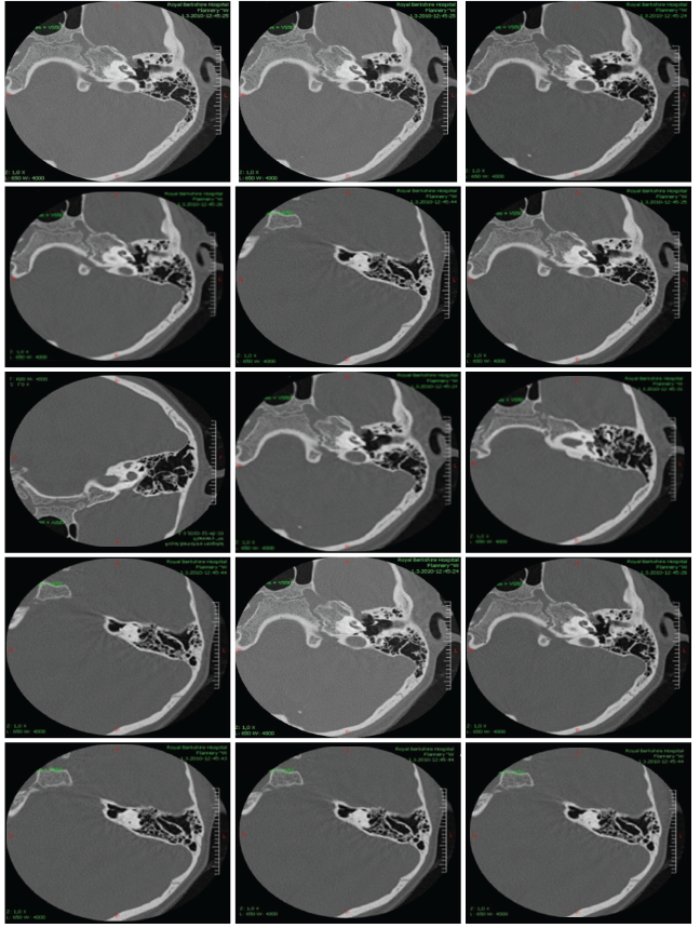

Branchio Oto Renal syndrome

Branchio Oto Renal Syndrome (BOR) is an autosomal dominant disorder with branchial, otologic and renal manifestations. The presence of clinical signs varies among and within affected families. Three causative genes for BOR syndrome have been reported thus far: EYA1, SIX1...